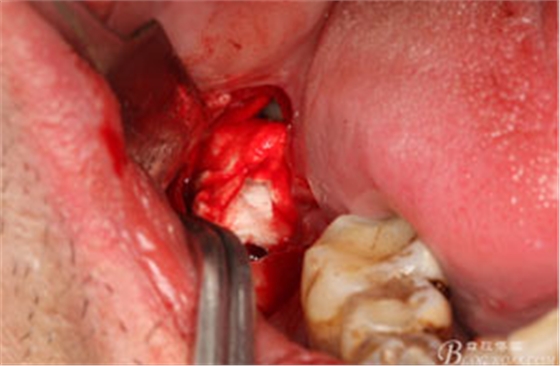

圖9.高速牙鉆分牙:

圖10.先頰舌向橫斷、然后再把牙冠近遠(yuǎn)中向縱分

圖11. “T”型的分牙。